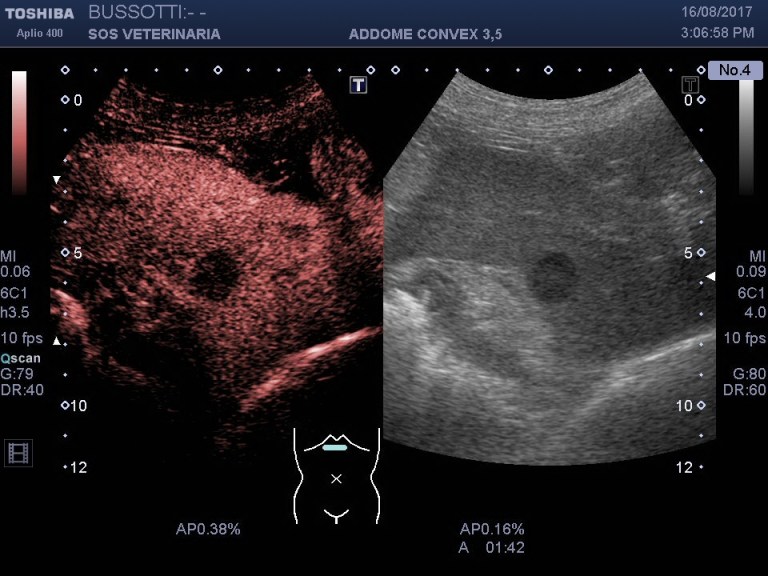

osservando la contrastografia ceus si evidenzia a livello epatico ipoenhancement anhancement delle lesioni focali tondeggianti e delle aree ventrali disorganizzate in tutte le fasi

il nodulo sul bordo splenico assume contrasto e lo dismette rapidamente rispetto al parenchima splenico rimanendo ipoenhancement

la contrastografia ,in questo caso non e’ stata essenziale per la diagnosi (l imaging in B mode era molto significativo) ma ha evidenziato la severita’ delle lesioni epatiche ,confermato la natura metastatica della malattia ,un eccezionale supporto quindi , ad una diagnosi ,fortemente sospetta che ha permesso ,in un momento non facile per il proprietario sopratutto e secondariamente per il medico curante, di prendere consapevolezza della gravita’ della malattia e accelerare l’ iter decisionale post diagnostico .